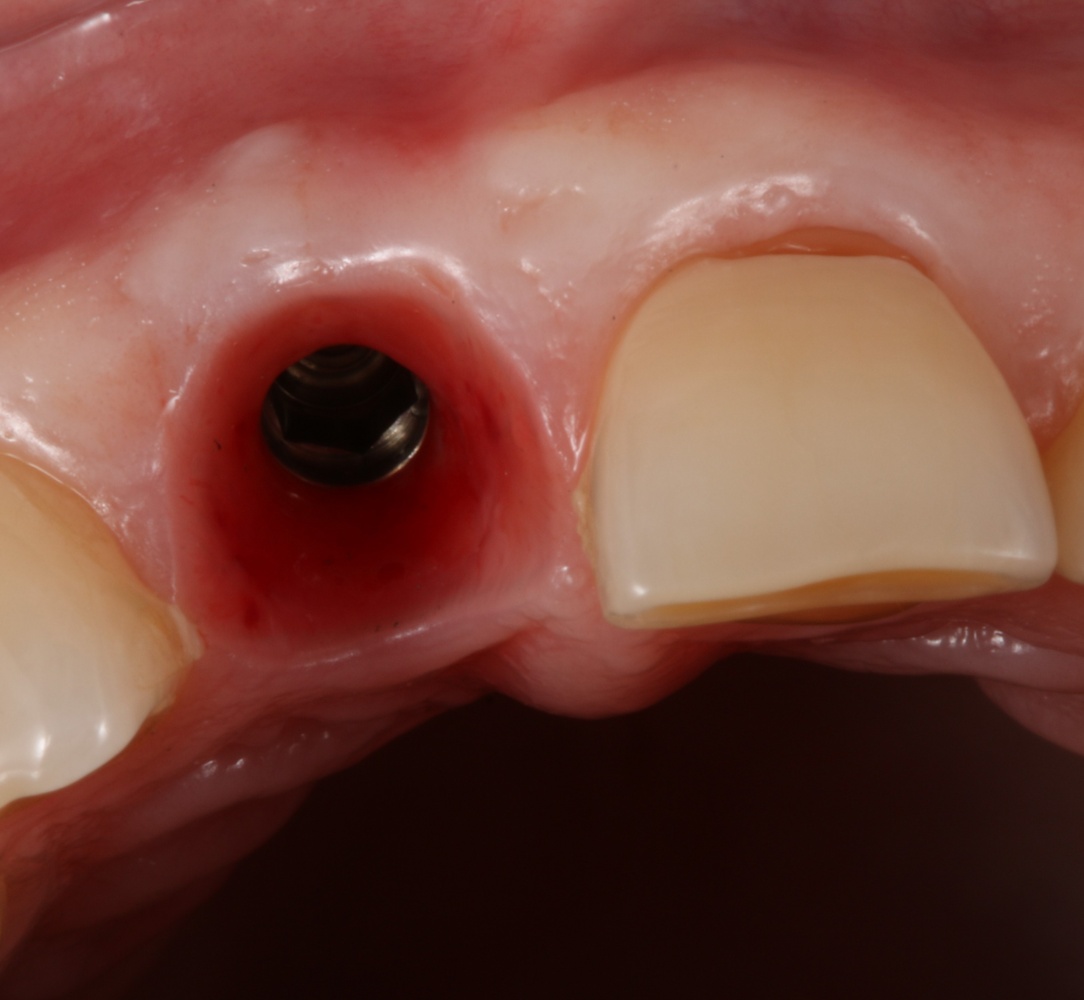

Однако, если одной из задач имплантологического лечения является максимальное сохранение окружающих зуб тканей, то без использования биоматериалов вряд удастся обойтись. На фотографии ниже: вроде как, проведена немедленная имплантация, но последующая атрофия альвеолярного гребня вконец испортила эстетический результат лечения.

Учитывая то, что имплантат (за редким исключением) всегда меньше, чем удаленный зуб, нам необходимо чем-то заполнить освободившееся от зуба пространство, чтобы удержать окружающие лунку ткани на месте. В противном случае, последующая атрофия может свести на нет эстетические результаты имплантологического лечения:

Согласитесь, не очень приятно, когда имплантат начинает просвечивать… и никакой, даже самой крутой коронкой это не компенсировать.